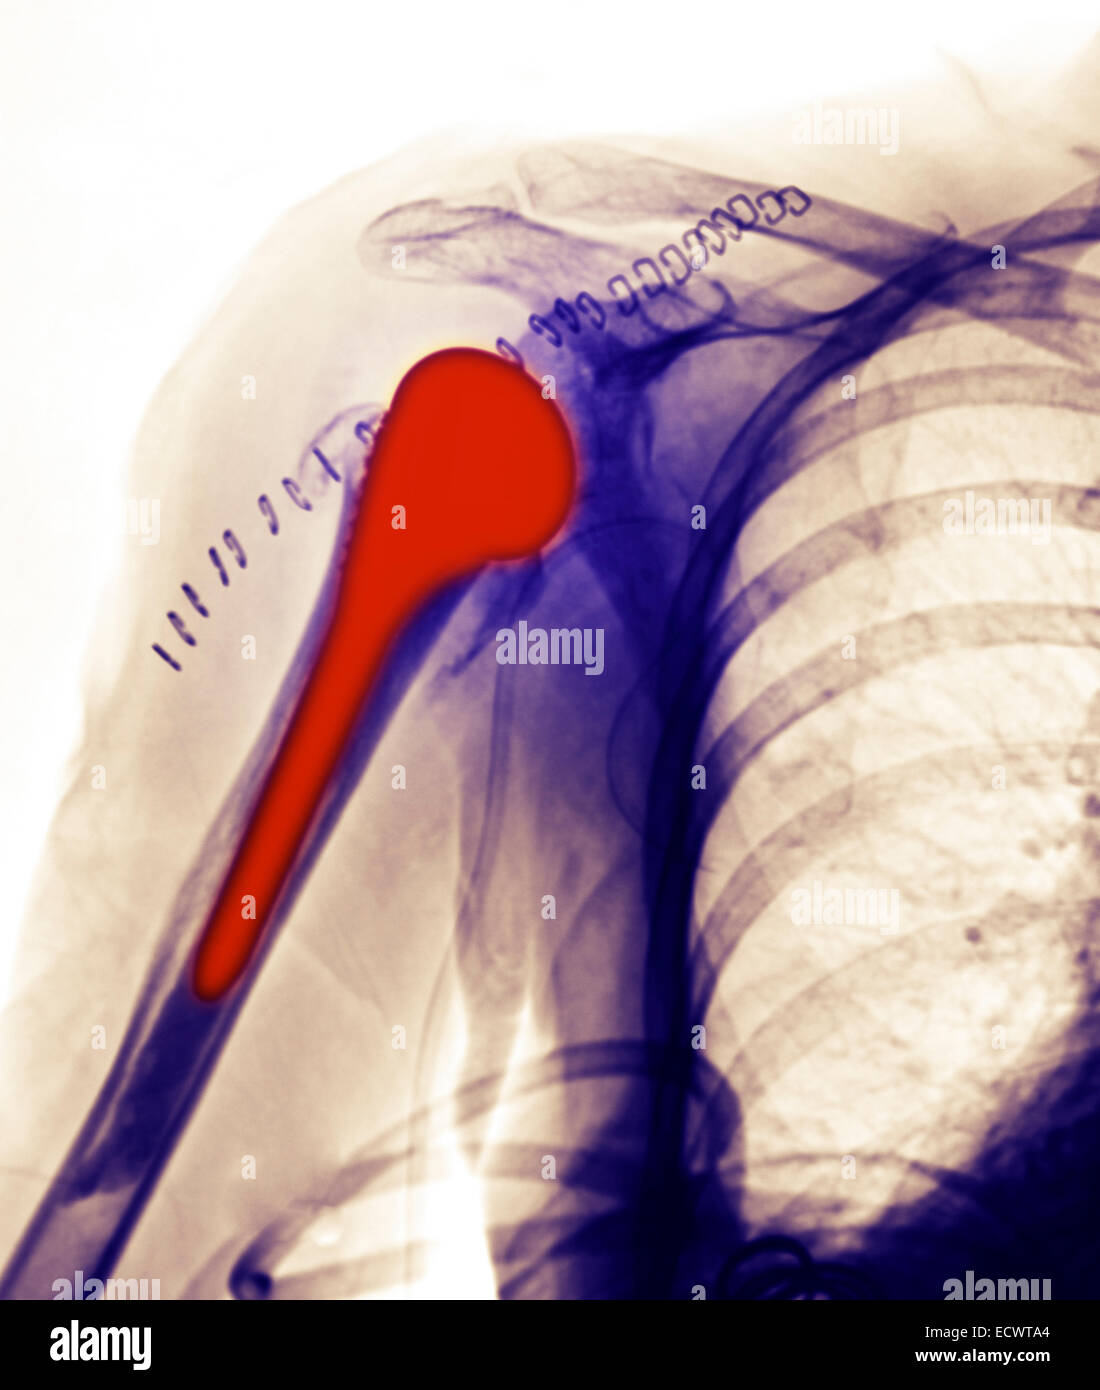

From www.alamy.com

xray showing a shoulder replacement Stock Photo Alamy Shoulder Replacement X Rays This article is chiefly limited to the routine radiographic evaluation of shoulder arthroplasties and guidelines to. shoulder replacement removes damaged areas of bone and replaces them with parts made of metal and plastic (implants). shoulder arthroplasty is the primary treatment of advanced glenohumeral arthritis once conservative measures fail, can restore function to. shoulder arthroplasties are a common. Shoulder Replacement X Rays.